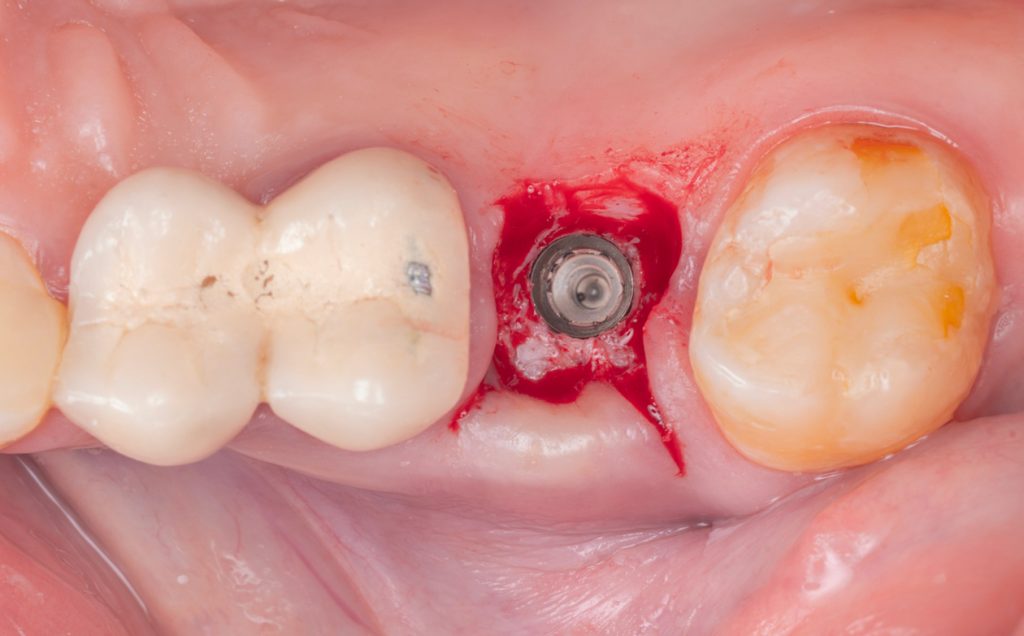

Implantacja natychmiastowa w odcinku bocznym i strefie estetycznej

Indywidualny kurs poświęcony implantacji natychmiastowej w odcinku bocznym i strefie estetycznej – oparty na biologii, analizie ryzyka i przewidywalności efektu estetycznego w czasie.

Zastosowanie obciążenia natychmiastowego w pracach pełnołukowych opartych na implantach. Kiedy chirurgia towarzyszy protetyce?

Najczęściej wybierane szkolenie przez lekarzy rozpoczynających pracę z pełnymi łukami. Szkolenie pokazujące prawdziwy, kliniczny workflow chirurg-protetyk, bez skrótów i uproszczeń – od kwalifikacji poprzez stabilne obciążenie natychmiastowe, po ostatnią śrubkę w pracy ostatecznej.